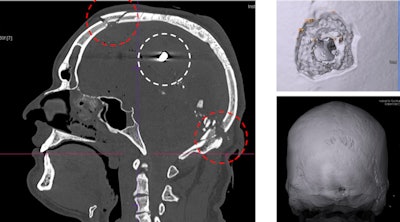

Gunshot injuries can be perfectly visualizised in 3D for court cases. Here, images show a gunshot with entrance wound in the neck area and bullet ricochet effect in the inner frontal part of the skull.

Gunshot injuries can be perfectly visualizised in 3D for court cases. Here, images show a gunshot with entrance wound in the neck area and bullet ricochet effect in the inner frontal part of the skull."Behind every body there is a family for whom we strive to answer questions without cutting up their loved ones," Thali said.